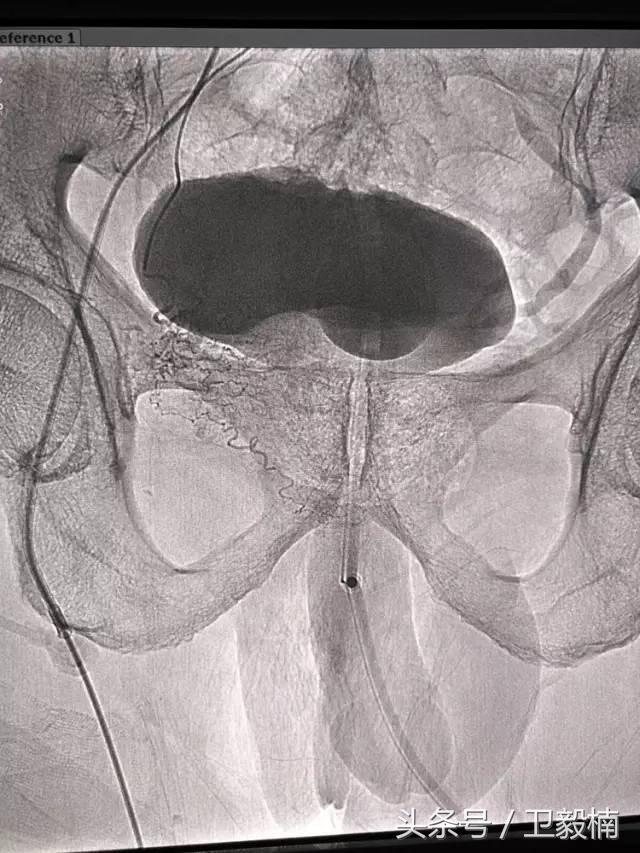

五、出血性疾病:鼻腔大出血、咯血、上消化道大出血、经皮肾镜术后出血、膀胱出血、产后出血等

七、子宫肌瘤、子宫腺肌症、宫外孕、输卵管阻塞引起的不孕症等妇产科疾病;

2、经导管血管栓塞法(Transcatheter embolization)

经原血管造影的导管或特制的导管,将栓塞物送至靶血管内,一是治疗内出血如外伤性脏器出血、溃疡病、肿瘤或原因未明的脏器出血。另一是用栓塞法治疗肿瘤,因肿瘤循环部分或全部被栓塞物阻断,以达控制肿瘤之生长,或作为手术切除的一种治疗手段;亦可用于非手术脏器切除,例如注射栓塞物质于脾动脉分支内,即部分性脾栓塞,以治疗脾功亢进,同时不影响脾脏的免疫功能。

(3)应用栓塞术治疗海绵状血管瘤,蔓状血管瘤,子宫肌瘤,骨肉瘤,鼻咽部纤维血管瘤等。